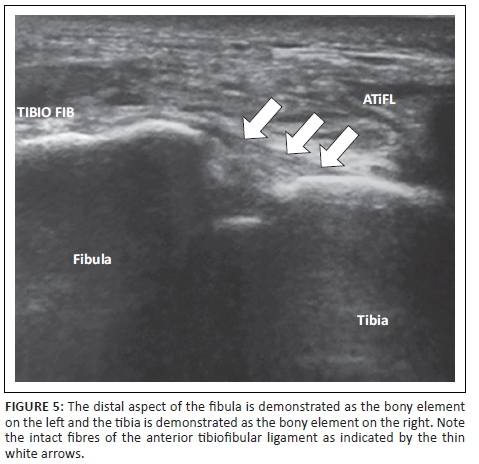

The transducer was placed transversely over the lateral aspect of the foot approximately 1 cm proximal to the ankle joint where the ligament is the thickest, while the posterior aspect of the transducer was placed just distal to the lateral malleolus. The squeeze test was performed during real-time imaging by pressing the tibia and fibula towards each other at the level of the mid-calf. With a syndesmosis injury, this manoeuvre elicits pain distally at the level of the distal tibiofibular syndesmosis.17 In order to evaluate the ATiFL for continuity, contour and haematoma formation, the anterior aspect of the transducer was rotated cranially and obliquely until the distal fibula and ATiFL were visible (Figure 5).

Images of the anatomical landmarks of the syndesmosis were obtained with the foot in neutral position (Figure 4) as well as in internal rotation. The cine loop facility enabled scroll back of the last frames to identify the image which demonstrated the maximum clear space distance. The tibiofibular clear space was measured at the deep border of the ligament, from the distal aspect of the fibula to the bony surface of the tibia, over the antero-lateral aspect of the ankle (Figure 6).